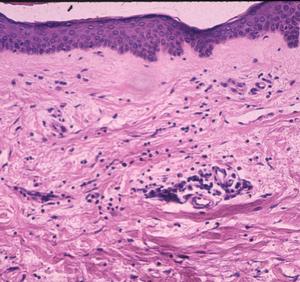

When examined by silver impregnation stain, this non-specific but suggestible infiltrate may be accompanied by spirochetes in the collagen. Rarely, the dermatitis may involve deeper vessels, even in the sub-dermal fat, which may resemble lupus erythematosus. Long-term infections have additional microvascular changes including angiopathy -- primarily occlusive changes similar to the post-capillary venulitis seen in syphilis.

Patients in Europe have been seen with a lesion of skin referred to as Borrelia lymphocytoma or lymphadenosis benigna cutis, usually involving the ear lobe, lateral neck skin, or areola of the nipple. The histology is instantly recognizable by a marked dermal infiltrate of lymphocytes and other mononuclear inflammatory cells totally, or nearly totally replacing the dermis, with well-formed germinal centers (Fig. 3), as seen in lymph nodes or tonsillar lymphoid tissue, hence the term lymphadenosis. This is a remarkable lesion clinically and pathologically and is not always caused by Borrelia infection. When it is, however, the clinician should look for the spirochetes, which can be seen by silver stains. Other examples of early disseminated infection, which may be seen days to weeks following tick bite, include meningitis, radiculoneuritis, encephalopathy and Bell's palsy.